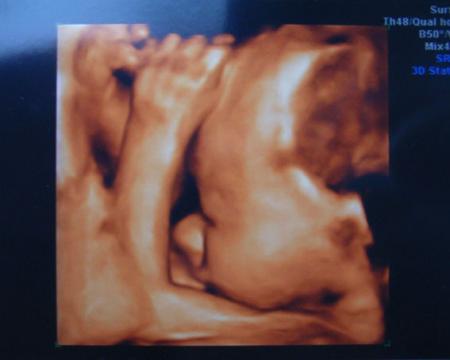

Er liegt jetzt auch endlich in SL und ich bekommen wieder Luft, ich hätte schon fast nen Sauerstoffzelt gebraucht *g* Allerdings mit dem Köpfchen nach hinten, er will sich einfach nich wirklich zeigen...3D Bildchen haben wir aber trotzdem bekommen, wenn auch nur von der Seite.

So hier die Bildchen